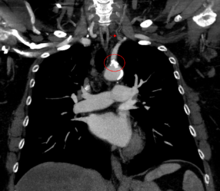

In medicine, subclavian steal syndrome (SSS), also called subclavian steal phenomenon or subclavian steal steno-occlusive disease, is a constellation of signs and symptoms that arise from retrograde (reversed) blood flow in the vertebral artery or the internal thoracic artery, due to a proximal stenosis (narrowing) and/or occlusion of the subclavian artery. The arm may be supplied by blood flowing in a retrograde direction down the vertebral artery at the expense of the vertebrobasilar circulation. This is called the subclavian steal. It is more severe than typical vertebrobasilar insufficiency.

SSS results when the short low resistance path (along the subclavian artery) becomes a high resistance path (due to narrowing) and blood flows around the narrowing via the arteries that supply the brain (left and right vertebral artery, left and right internal carotid artery). The blood flow from the brain to the upper limb in SSS is considered to be stolen as it is blood flow the brain must do without. This is because of collateral vessels.

In SSS a reduced quantity of blood flows through the proximal subclavian artery. As a result, blood travels up one of the other blood vessels to the brain (the other vertebral or the carotids), reaches the basilar artery or goes around the cerebral arterial circle and descends via the (contralateral) vertebral artery to the subclavian (with the proximal blockage) and feeds blood to the distal subclavian artery (which supplies the upper limb and shoulder).